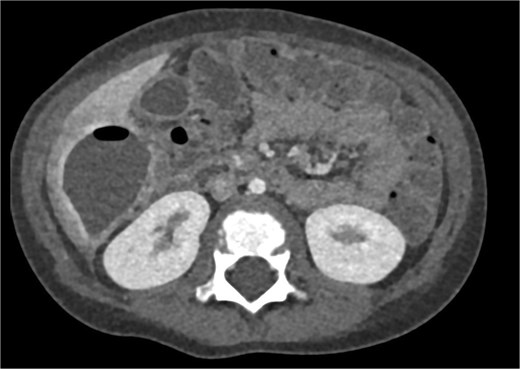

CT imaging of the abdomen (Fig. 2) revealed a retrocecal appendix in its typical location, measuring 50 mm in length and 14 mm in diameter, with a thickened wall (5.5 mm). A proximal fecalith measuring 3 × 3 × 14 mm was identified. Post-contrast enhancement of the appendix wall was noted. Adjacent to segments V and VI of the liver, a fluid collection with an air-fluid level was observed, measuring 5.3 × 3.8 × 4.5 cm, surrounded by a 3 mm enhancing capsule, consistent with a hepatic abscess. A second, smaller hypodense collection measuring 13 × 22 × 11 mm was found inferior to the primary abscess. Additional findings included reactive lymphadenopathy (up to 8 × 4 mm) and free fluid in the right iliac fossa (up to 12 mm). Other abdominal organs, including the liver, pancreas, kidneys, and spleen, appeared normal. The findings were consistent with complicated acute appendicitis and associated abscesses.

CT imaging of acute appendicitis with fecalith and multiple hepatic abscesses.

Imaging plays a crucial role in diagnosing appendicitis and its complications. Ultrasound is often the initial modality used, but it may have limited sensitivity in detecting intra-abdominal abscesses, particularly when the appendix is not visualized or when findings are inconclusive [4, 5]. In such cases, contrast-enhanced CT is considered the gold standard, providing detailed visualization of the appendix and associated complications, including abscess formation [2, 4]. In the present case, the initial ultrasound findings suggested an atypical position of the appendix and a pathological fluid collection, but CT imaging confirmed a retrocecal appendix and subhepatic abscesses (Figs 4 and 5), guiding appropriate management.

CT axial view of a subhepatic abscess. Contrast-enhanced capsule and fluid-air level visible.